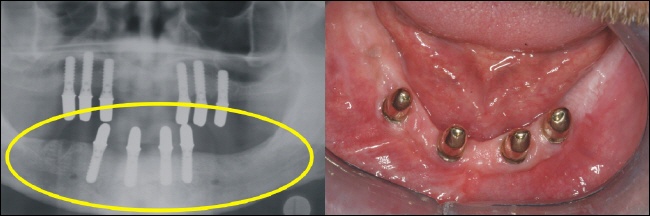

Das Bild rechts zeigt den zahnlosen Oberkiefer. Im Röntgenbild sieht dies aus wie auf dem linken Bild (gelber Kreise). |

Der zahnlose Unterkiefer rechts im Bild bietet keinen Halt mehr für eine Prothese. Links zeigt sich der zahnlose Knochenabschnitt im Röntgenbild (gelber Kreis). |